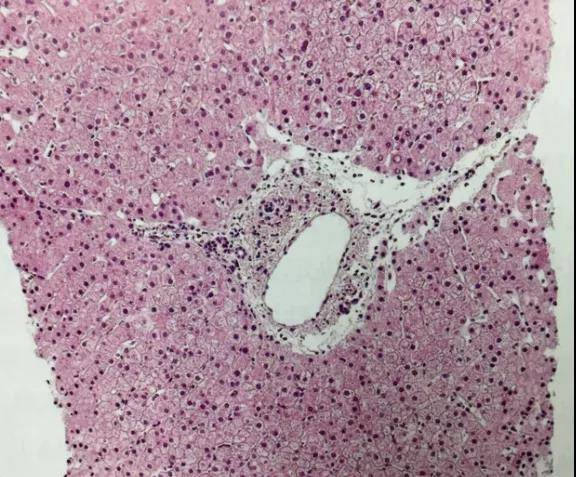

图1. 免疫性肝炎患者经过3年免疫抑制治疗后获得了临床缓解,肝穿刺提示肝组织活检未见异常。